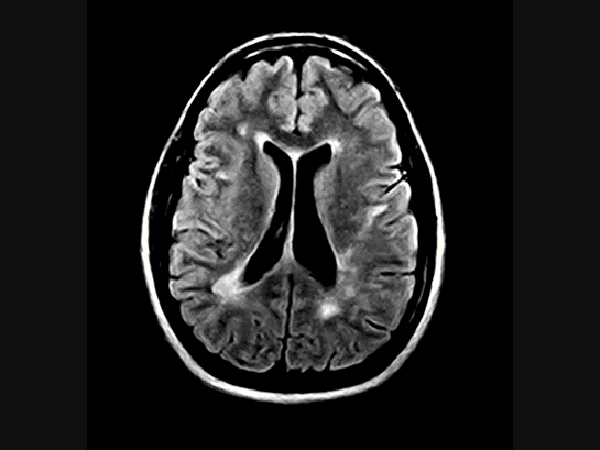

Klinické snímky